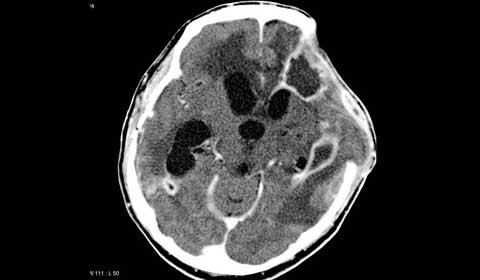

Áp-xe não. Là những ổ nhiểm khuẩn khu trú trong nhu mô não gây mủ. Thường áp-xe não gây viêm màng não mủ. Áp-xe não gây tỷ lệ tử vong rất cao và biến chứng nặng nề. Chẩn đoán như lâm sàng tràn dịch dưới màng cứng nhờ siêu âm và scanner. Điều trị bằng cách dẫn lưu mủ, bóc tách và kháng sinh.